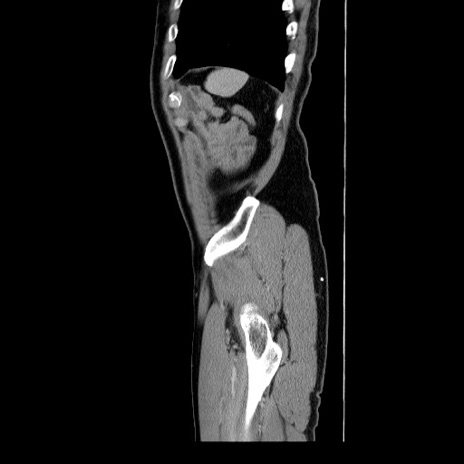

横断像